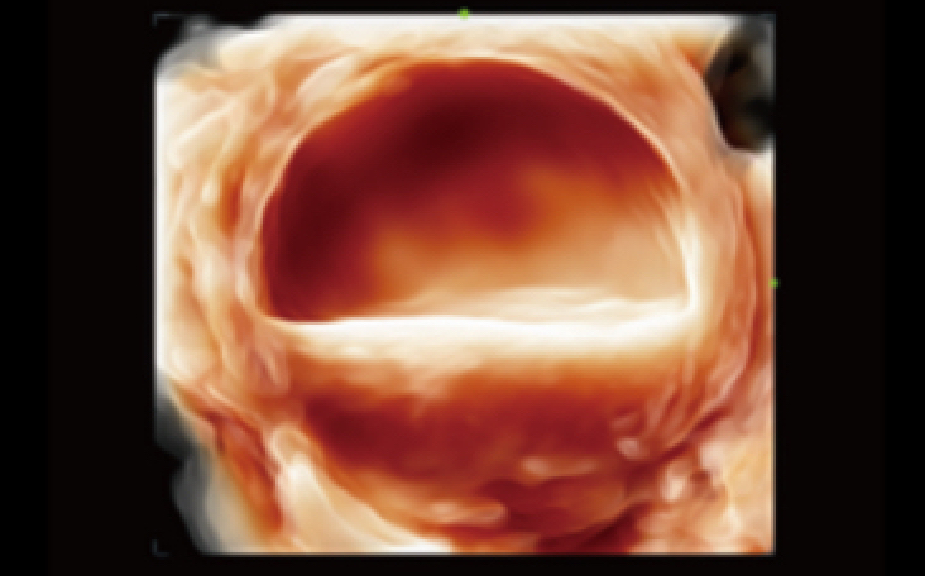

Smart Pelvic

En vistas de la creciente importancia del diagnĂłstico por ecografĂa en los trastornos del suelo pĂ©lvico, Smart Pelvic ofrece una nueva soluciĂłn para simplificar en gran medida los procedimientos y minimizar el tiempo de examen para una evaluaciĂłn estandarizada. Con una interacciĂłn con el usuario extremadamente simple, genera un sistema de coordenadas estĂĄndar y proporciona todas las mediciones relacionadas automĂĄticamente en unos pocos segundos.